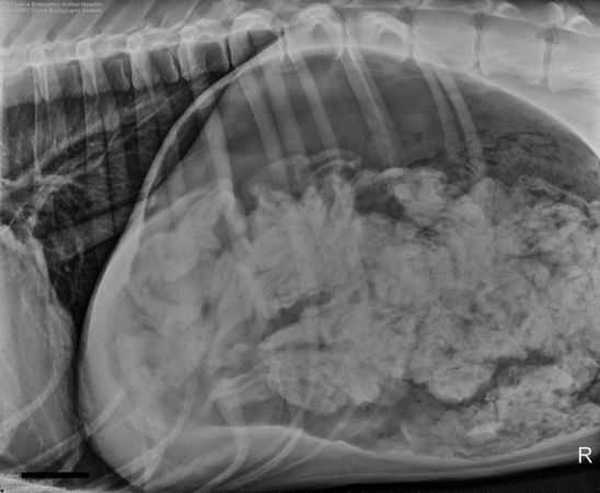

После того, как хозяева четвероногого пациента ответили на все вопросы ветеринаров и заполнили документы, доктор Эшли Маги (Ashley Magee) отвела собаку на рентгенологическое исследование. Полученный снимок насторожил специалистов - в желудке дога находилось большое количество инородных предметов.

“Инородные предметы скопились в желудке и их было настолько много, что они явно не могли быть переварены, - объясняет сотрудница больницы Шона Хач (Shawna Harch). - Это означало, что собаке придется делать операцию”.

Эта история стала достоянием общественности после того, как врачи предоставили рентген для участия в конкурсе журнала для ветеринаров на самые необычные находки, обнаруженные внутри животных. Несмотря на поразительное количество съеденных собакой носков, ветеринары из Портленда заняли третье место, отмечает Los Angeles Times.